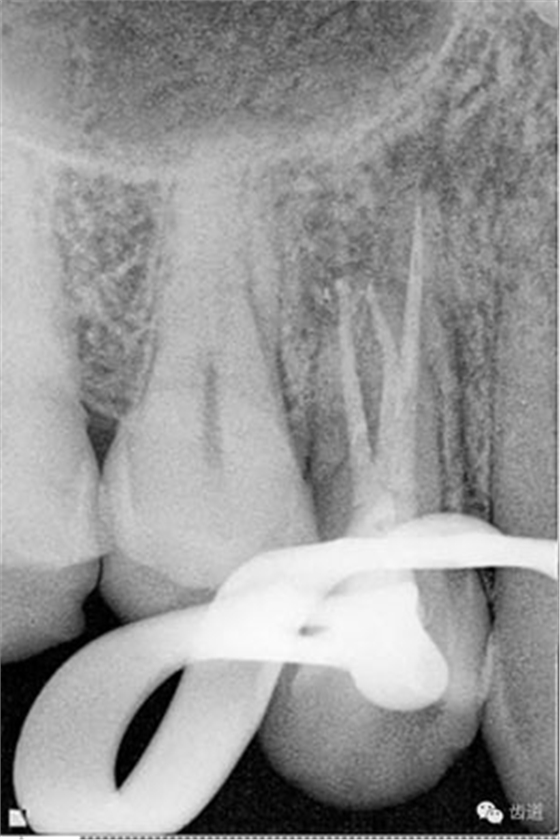

處理:放置橡皮障,去除暫封,超聲結(jié)合2%CHX清除遠(yuǎn)頰根管內(nèi)氫氧化鈣糊劑,主牙膠試合后95%酒精沖洗干燥根管,結(jié)合AHPlus糊劑連續(xù)波熱牙膠垂直加壓充填根管,樹(shù)脂分層粘接修復(fù)牙體。建議定時(shí)復(fù)診進(jìn)行嵌體修復(fù),患者未執(zhí)行。